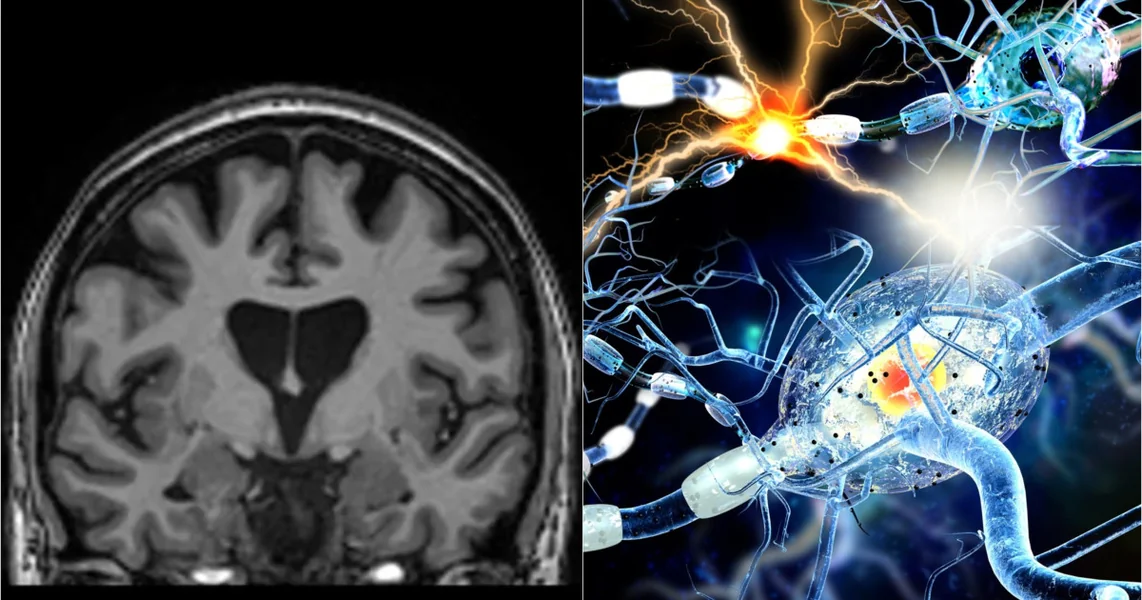

Nova studija Univerziteta Griffith (NCNED) koristi multimodalnu MRI za procenu zdravlja mozga kod osoba kojima je ranije dijagnostikovan COVID-19, upoređujući ih sa učesnicima bez infekcije. Rezultati pokazuju jasne promene u sivoj i beloj masi koje su prisutne i kod osoba koje se smatraju potpuno izlečenima, te je veza između stepena promena i težine simptoma kod post-COVID sindroma. Studija naglašava potencijalne posledice po kogniciju i dugoročnu zdravlje mozga, objavljeno u Brain, Behavior, & Immunity - Health.